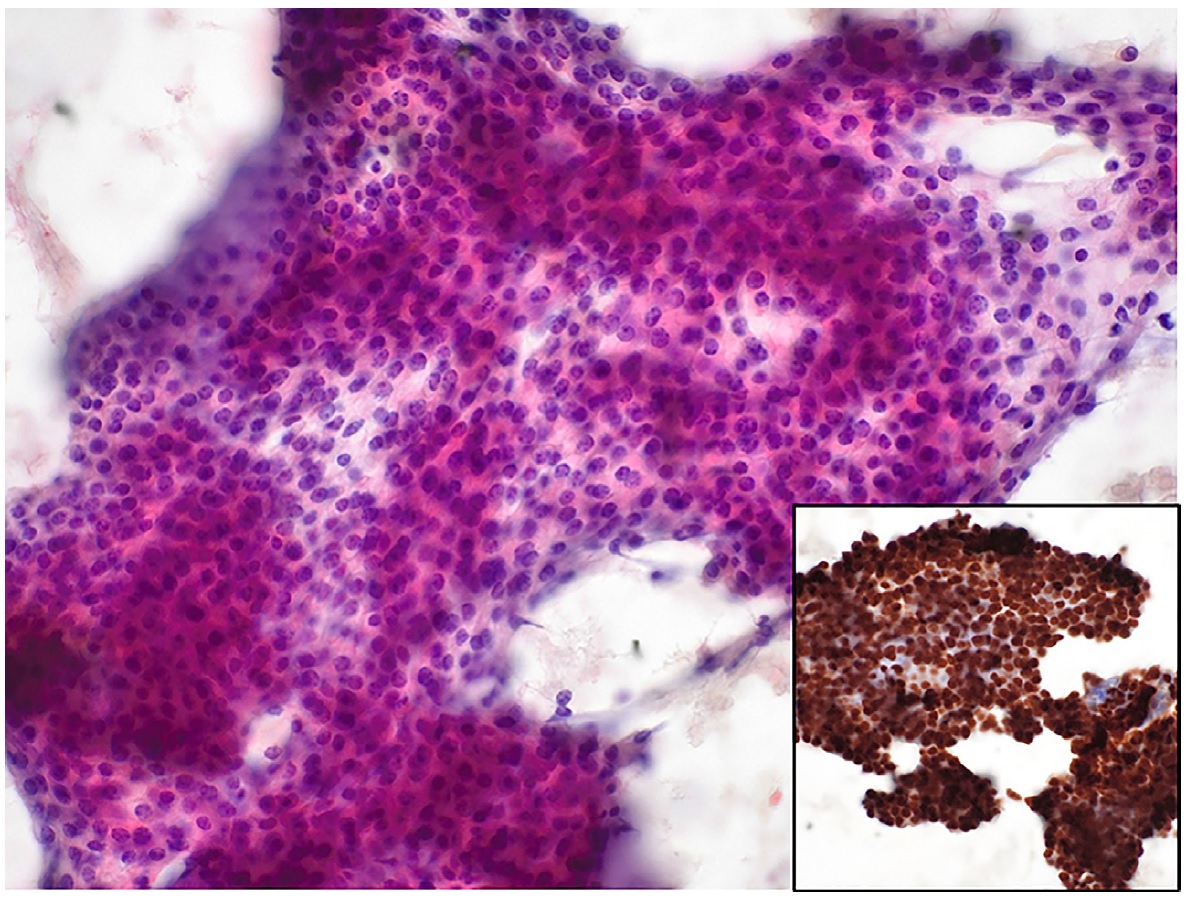

Иллюстрации и схемы по остеопорозу и паращитовидной железе